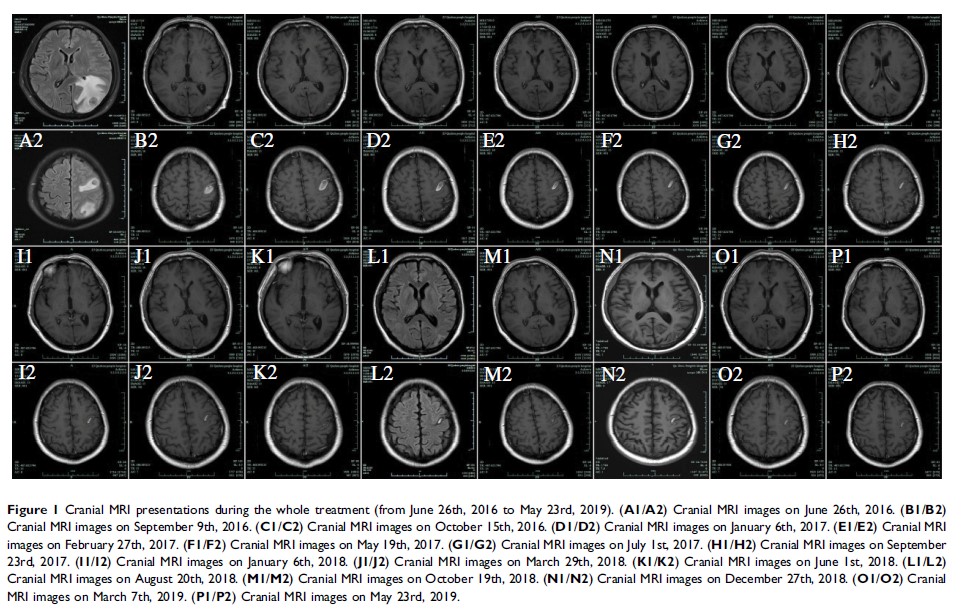

Case Report

伴有症状性脑转移的肺腺癌在系统治疗后的放射学完全缓解:病例研究